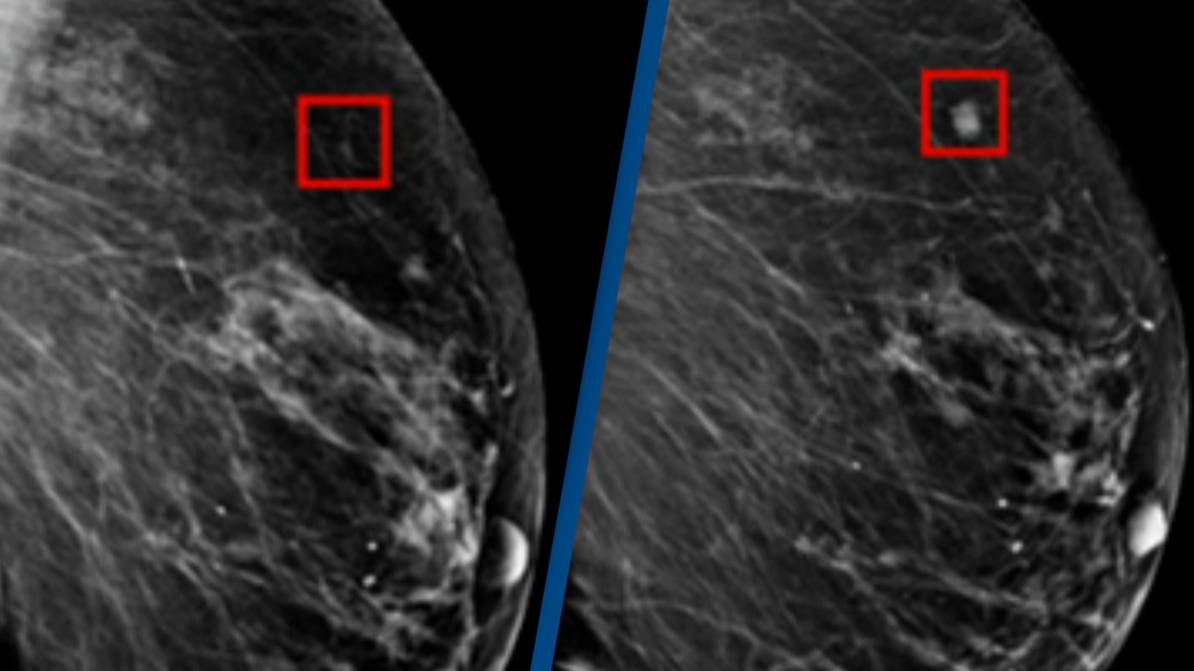

A study conducted by Swedish researchers suggests that radiologists assisted by artificial intelligence (AI) are more effective at detecting breast cancer than two radiologists working together. The study compared the performance of radiologists working with AI to that of human radiologists in screening mammograms from over 55,000 women. The addition of AI to the screening process resulted in a four percent increase in breast cancer detection and reduced false positives, potentially improving accuracy and reducing unnecessary imaging and biopsies. The researchers believe that AI has the potential to take over the majority of screening mammography assessments in the future.